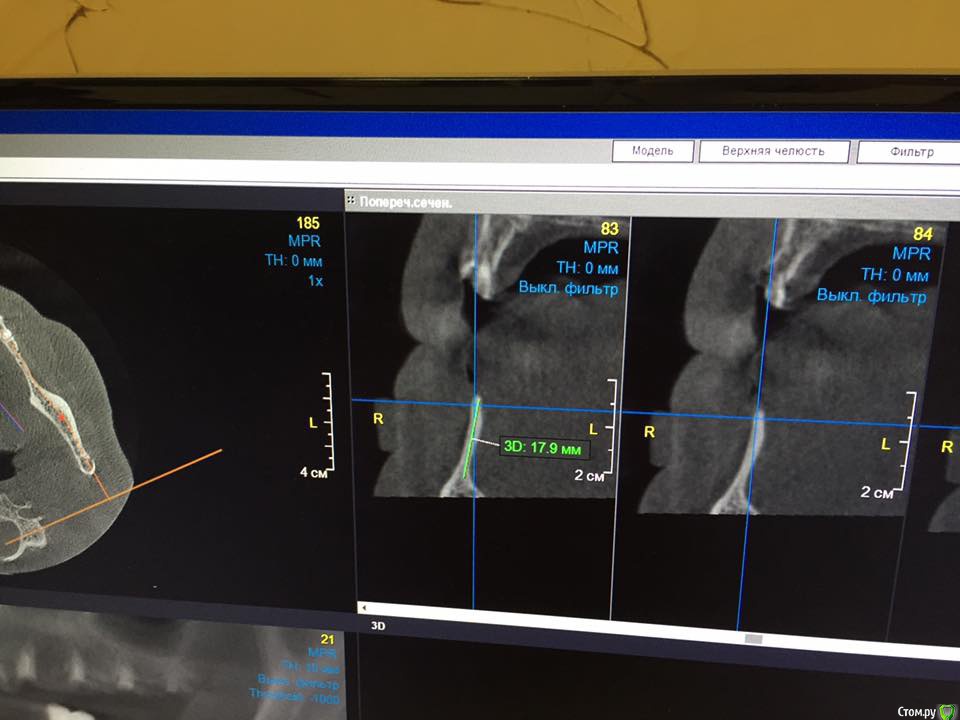

EEcho Опубликовано 30 января, 2017 Автор Поделиться Опубликовано 30 января, 2017 покажите срезы дальше(дистальнее) может целесообразно провести аугментацию дистально, возможно там ситуация получше... и сделать медиальную консоль на 5ый зуб.Срезы в области 45, 46, 47,48, Ссылка на комментарий

kamranchick Опубликовано 28 января, 2017 Поделиться Опубликовано 28 января, 2017 Уважаемые коллеги!Прошу совета!? Как увеличить объём, каким методом? Я в затруднении. За ранее большое спасибо!покажите срезы дальше(дистальнее) может целесообразно провести аугментацию дистально, возможно там ситуация получше... и сделать медиальную консоль на 5ый зуб. 1 Ссылка на комментарий